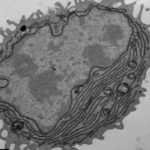

I ricercatori della Southampton stanno studiando come il farmaco funziona e come superare la resistenza. Essi hanno dimostrato che rituximab funziona stimolando specifiche cellule del sistema immunitario chiamate macrofagi, a “mangiare” le cellule del linfoma.

Tuttavia, alcuni linfomi sono in grado di sopprimere i macrofagi manipolando le proteine ​​chiamate recettori Fc-gamma presenti sulla loro superficie, per prevenire l’assorbimento. I risultati di questo studio aiutano a spiegare perché rituximab può essere inefficace in alcuni pazienti affetti da linfoma.